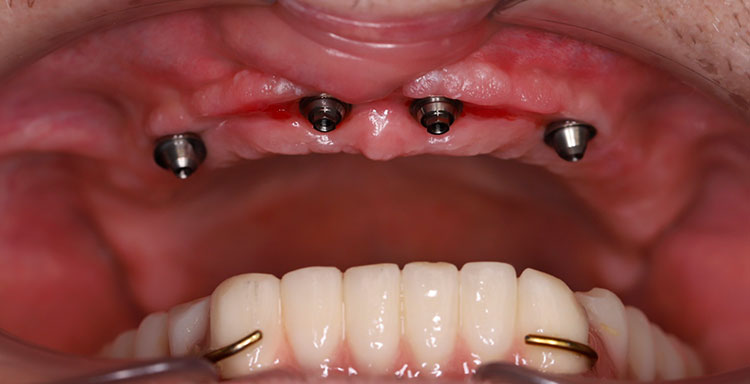

Под местной анестезией по ранее изготовленному хирургическому шаблону установлены 4 импланта Medentika Quadroconne (3.8х09 в область 1.1, 2.1, 4.3х11 в область 1.3, 2.3 под углом 30 гр.), получен необходимый торк, установлены мультиюниты, получен оттиск для изготовления временного пластмассового протеза. Установлены защитные колпачки, рана ушита. Даны назначения (Антибиотики, НПВС).

Через 5 дней сняты швы, установлен временный пластмассовый мостовидный протез, проведена коррекция.